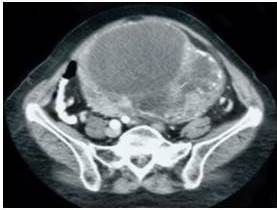

El examen físico mostró temperatura de 37,5°C, pulso de 81 latidos por min, frecuencia respiratoria de 17 respiraciones por min y la presión arterial de 146/84 mm de Hg. La evaluación abdominal demostró tumoración no dolorosa en hemiabdomen inferior sin alteraciones neurológicas periféricas. Las pruebas de laboratorio estaban dentro de límites normales. La ecografía abdomino-pélvica que reportó gran tumoración encapsulada, ovoidea y blanda de 20 cm de diámetro que sugería la posibilidad de tumoración ovárica. La tomografía confirmó la presencia de tumoración pélvica hiper ecogénica, compleja, poli-lobulada, que contenía tabiques internos, áreas sólidas periféricas y calcificaciones periféricas que se extendía desde la aorta inferior a nivel del sacro que medía 20 cm x 19 cm de diámetro que desplazaba los vasos pélvicos sin evidencia de infiltración a las estructuras que lo rodeaban, sugiriendo la posibilidad diagnostica de cistoadenoma de ovario (Figura 1). Sin embargo, no se pudo establecer el origen de la lesión. Los marcadores tumorales fueron negativos. La cistoscopia y rectosigmoidoscopia excluyeron la posible afección urológica e intestinal. En vista de los hallazgos clínicos de imágenes y de laboratorio se consideró que la lesión era benigna y se programó la cirugía debido al origen incierto y tamaño del tumor.